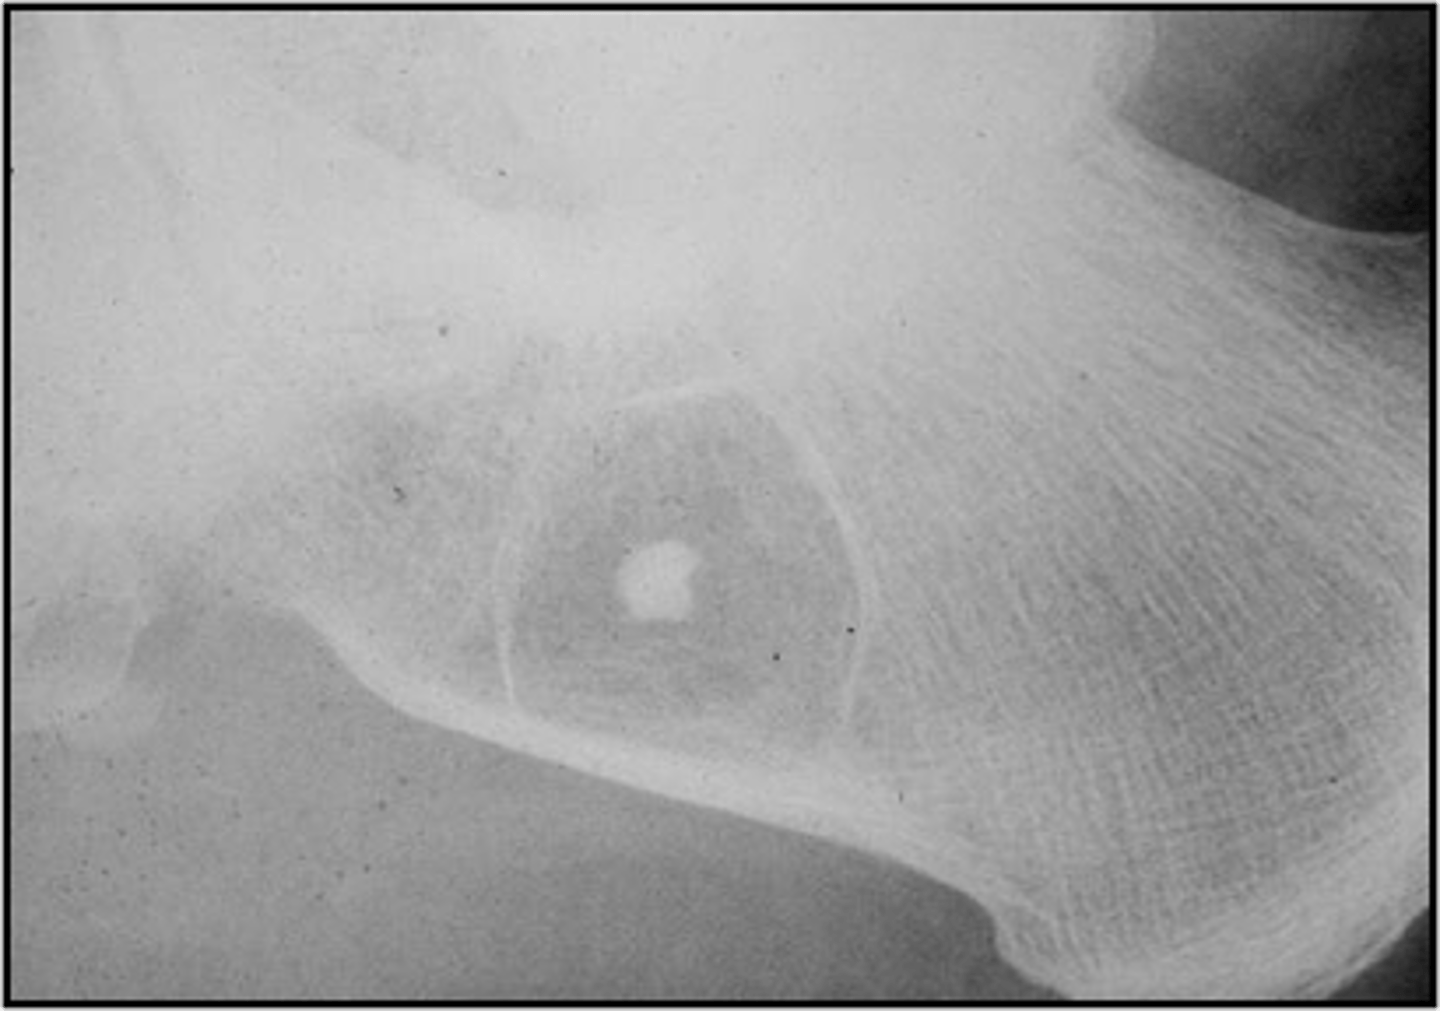

Target sequestrum

ID sign of intraosseous lipoma

<p>ID sign of intraosseous lipoma</p>